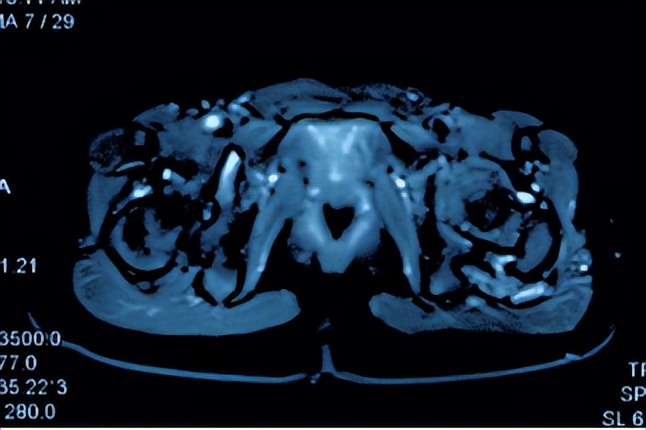

患儿家长近期发现孩子说左侧屁股疼痛,肉眼可见左侧臀部肿胀,鼓包。家长先后就诊于多家医院行超声,X线等检查,超声提示左臀部髋关节后方肌层内低回声肿物,考虑血管瘤。核磁检查提示左髋后侧股方肌见不规则团块状占位性病变,大小约39*25*48mm。考虑血管瘤?通过网上查询,发现我院在血管瘤和脉管畸形治疗方面很有经验。遂来到我门诊看病。在看过病人后,结合超声,MRI以及化验检查,考虑患儿应该是左臀部的静脉畸形。这种低流速的血管畸形表现为静脉扩张或局部海绵状肿块,涉及多个组织和器官。在早晨起床、寒冷天气或长时间运动时出现疼痛。当合并局限性凝血功能异常时,则表现为更明显、更持久的疼痛,并伴有明显的肿胀和异常感觉。立即安排了相关术前检查,并抓紧安排住院治疗。

MRI提示 血管畸形